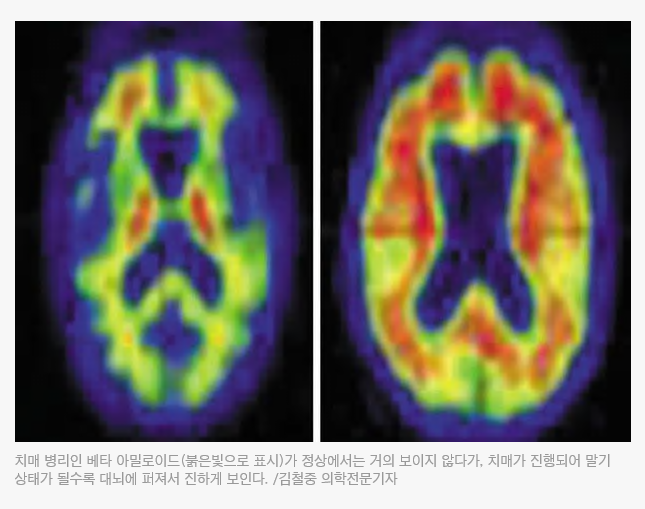

치매 병리인 베타 아밀로이드(붉은빛으로 표시)가 정상에서는 거의 보이지 않다가, 치매가 진행되어 말기 상태가 될수록 대뇌에 퍼져서 진하게 보인다. /김철중 의학전문기자

치매 병리는 대뇌에 베타 아밀로이드라는 변형 단백질이 침착하는 것이다. 이는 머리를 쓰면 자연스럽게 생겨나는 대사물질이지만, 정상적으로 제거돼야 한다. 제거가 안 되고 뇌에 쌓이고 뭉치면 뇌세포가 손상된다. 그러다가 뇌에 넓은 범위로 늘어나면 치매 진행이 가속화 된다. 모두 일치하는 것은 아니지만, 치매 단계가 진행될수록 아밀로이드 침착은 늘어난다.

따라서 뇌 사진을 찍어서 아밀로이드 침착 정도를 파악한다면 조기 치매 발견은 물론 치매 진행 상황도 파악할 수 있다. 그런 배경 속에서 나온 것이 아밀로이드 PET-CT(양전자 컴퓨터 단층촬영)이다. 뇌에 베타 아밀로이드가 쌓여 가는 정도를 영상 이미지로 볼 수 있다. /영상의학과 전문의